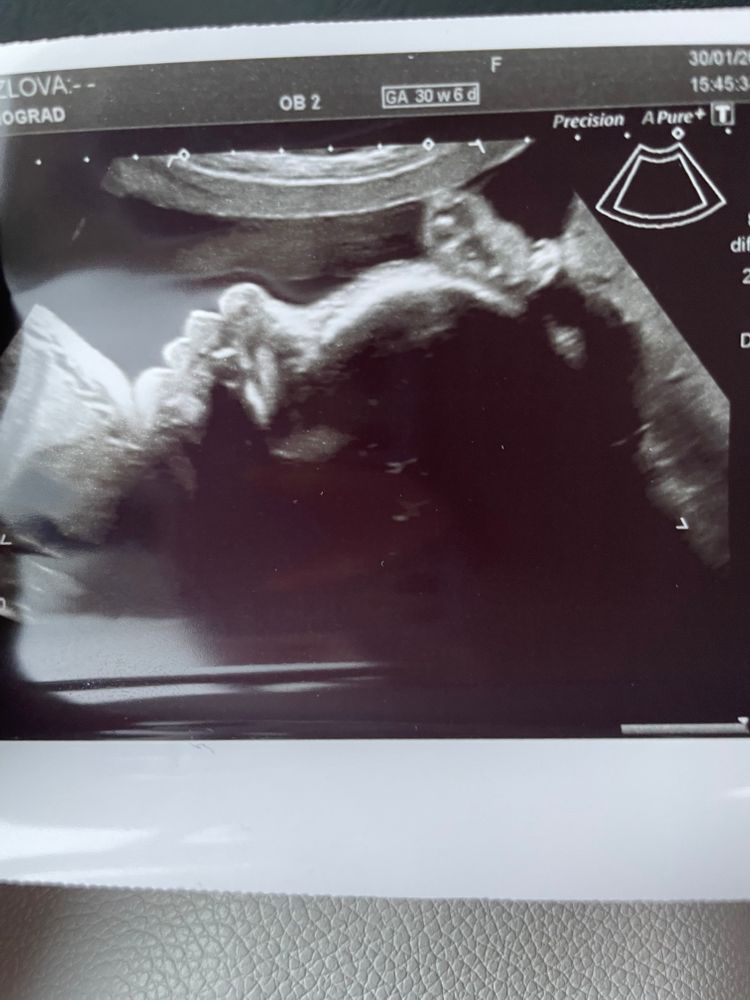

3 скрининг - 30+6 недель

30.01.2023